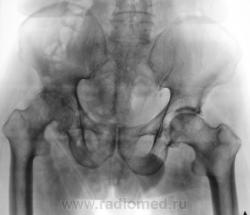

В принципе, болеть есть от чего. Однако, у меня на подозрении очаги разрежения структуры в головке левой бедренной кости и в теле правой подвздошной кости над вертлужной впадиной. Очаги весьма четкие, круглые - дообследуйте на предмет миеломной болезни.

Справа на фоне лонной и седалищной костей по-видимому тени кишки - грыжа?

Бластического варианта НЕТ. Очаги просветления, в данном случае -затемнения газ в к-ке. ДОА пр.т/б сустава 4 , левого - 2 степени, артрозные изм-я в сакроилеальных сочленениях, выраженней в левом

Правая половина таза меньше за счёт проекционного искажения?

Да, положение вынужденное.